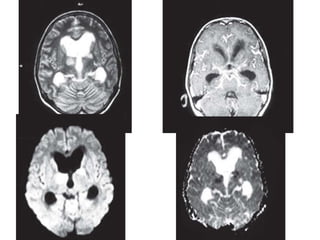

Postcontrast T1W axial (A) and coronal (B) MR

images showing diffuse meningeal

enhancement along the cerebral

convexities, tentorium and the basal cisterns

with hydrocephalus — tubercular meningitis

MRI

• MRI may be normal in early stage

• Later, there may be widening of the

subarachnoid spaces with associated T1 and

T2 shortening of the CSF.

• Postcontrast T1-weighted MR images show

diffuse meningeal enhancement, mainly at the

basal cisterns and the sylvian fissures